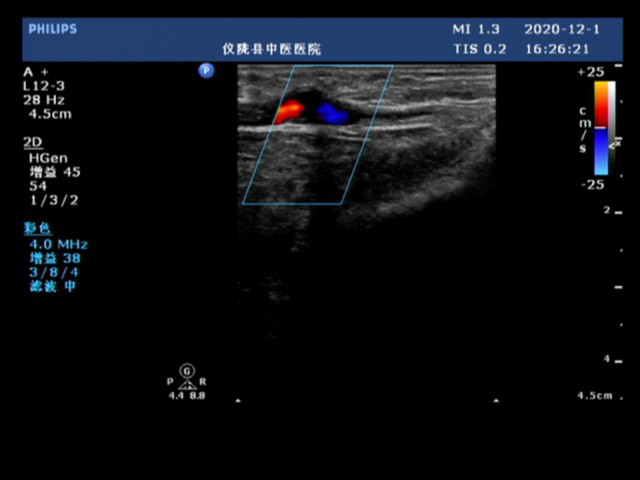

(2)血管瘤样扩张:长期静脉高压、血管过于表浅、不正确的穿刺方法可导致血管瘤样扩张,多发生在内瘘静脉侧。超声表现为内瘘静脉侧囊状无回声扩张,内可见漩涡样「红蓝」血流信号,常伴有血栓形成。